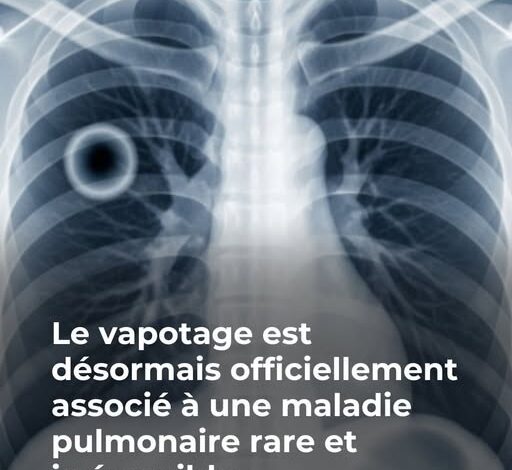

Ses amis l’avaient pourtant mis en garde contre les risques pour la santé liés au vapotage. Cependant, James pensait être à l’abri des conséquences graves. Cette idée l’a mené à une situation critique, le laissant avec un seul poumon en état de marche et un pronostic de vie sévèrement écourté s’il ne change pas ses habitudes de vie.

La situation de James s’est brusquement aggravée un soir lorsqu’il a commencé à vomir du sang. Il a été transporté d’urgence en soins intensifs et placé sous oxygène, avant d’être mis dans un coma pour tenter de sauver ses poumons.